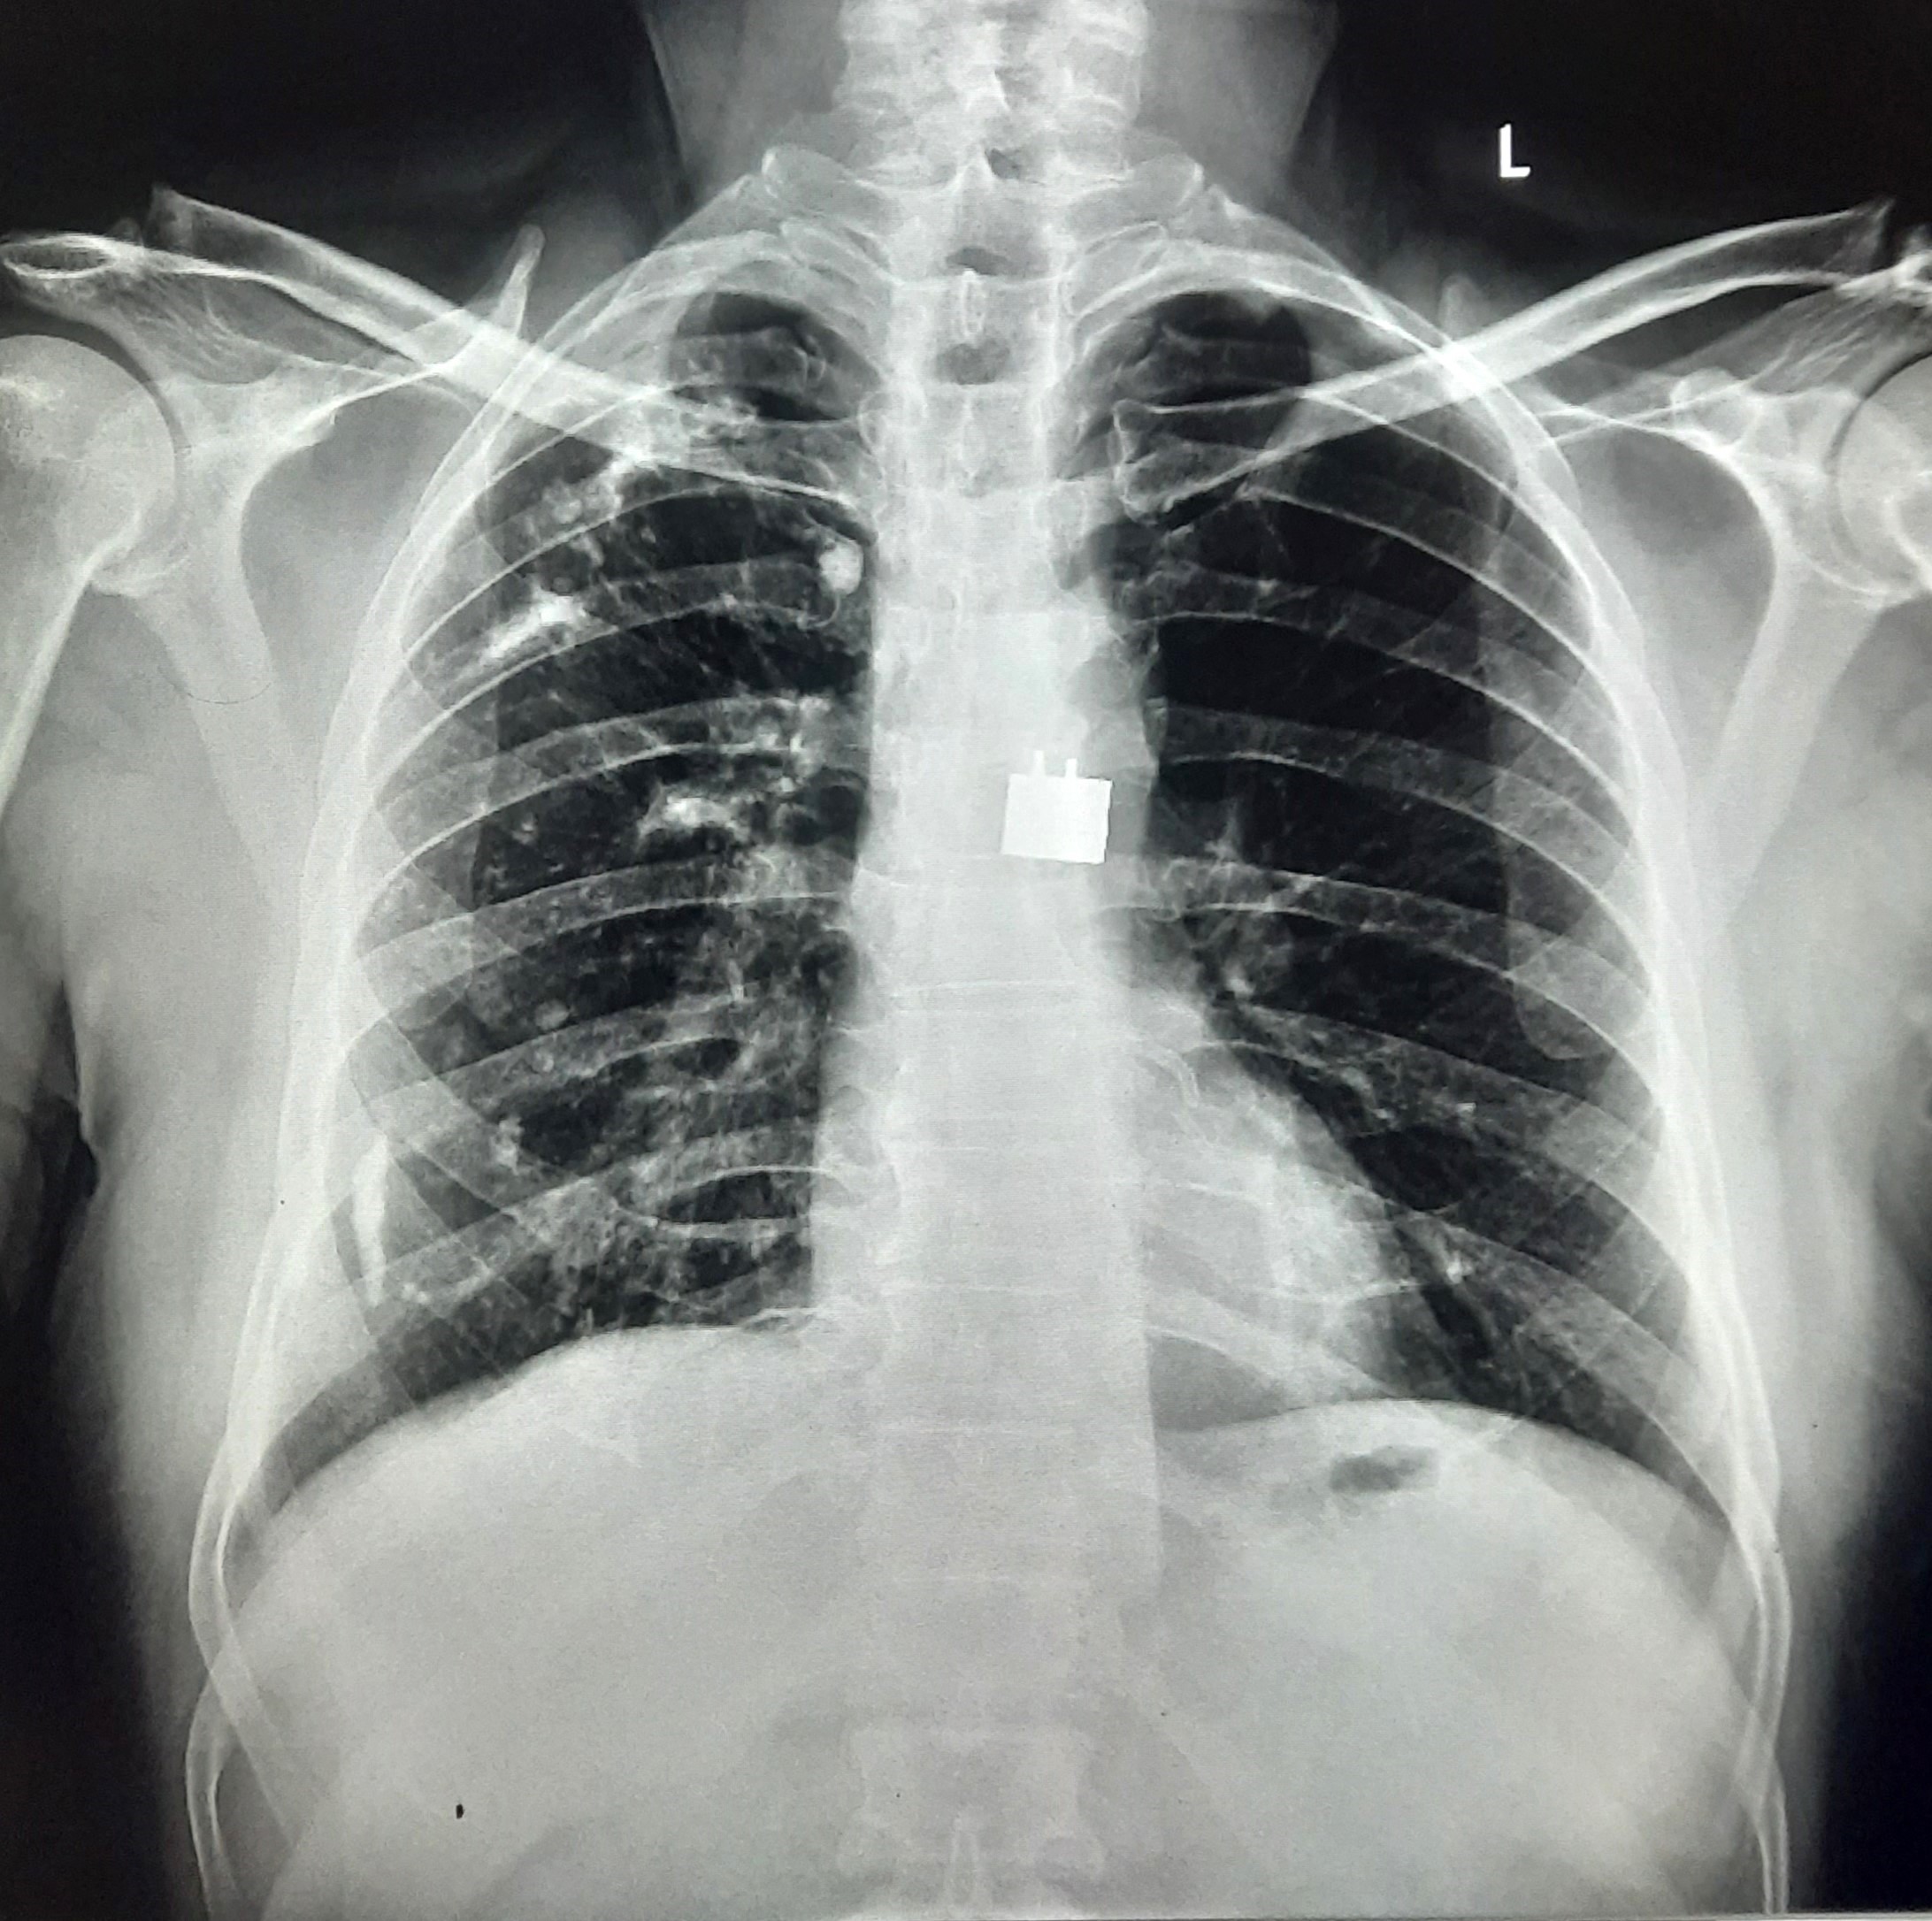

| 153 | IGGMC, Nagpur, Nagpur | P2 | 29-4319 | Irfan Ahmad | Consent taken on Paper | 59 Yrs. |

Provisional Diag : ?

Final Diag : Post TB Sequel With Reactivation |

Post TB Sequelae | Right Upper Zone/ Middle Zone Infiltration With Right Lower Zone Homogenous Opacity With Calcification | Abnormality visible on x-ray |